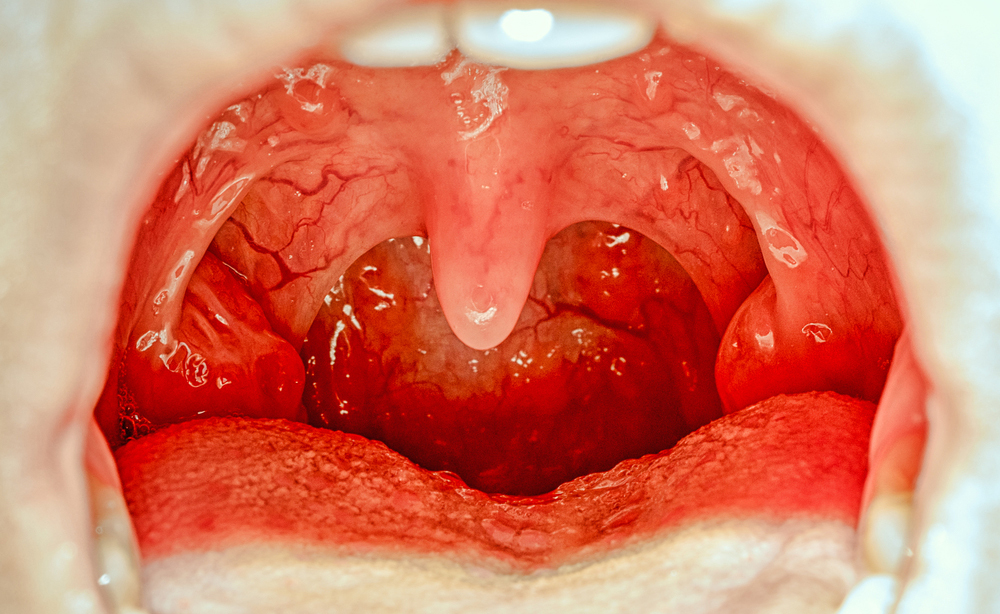

Il palato può essere suddiviso in due parti: il palato duro posto davanti e il palato molle, nella parte posteriore. L’ugola si trova proprio al centro di questa divisione, all’interno della gola, ed è principalmente composta da membrana mucosa, tessuto connettivo e muscolare e i canali dai quali fuoriesce la saliva.

Sebbene sia piuttosto raro, l’ugola e le sue circostanti possono gonfiarsi a causa di rossore e indolenzimento. Proprio tali infiammazioni costituiscono la risposta automatica dell’organismo a lesioni, reazioni allergiche e malattie. Questa risposta immunitaria può causare uvulite, e provoca:

Quando il sistema immunitario non è in grado di contrastare le minacce che intaccano l’organismo, come virus e batteri, l’ugola si infetta, provocando quella fastidiosa sensazione di avere qualcosa incastrato in gola, difficile da ingoiare. Altri sintomi legati all’uvulite sono: